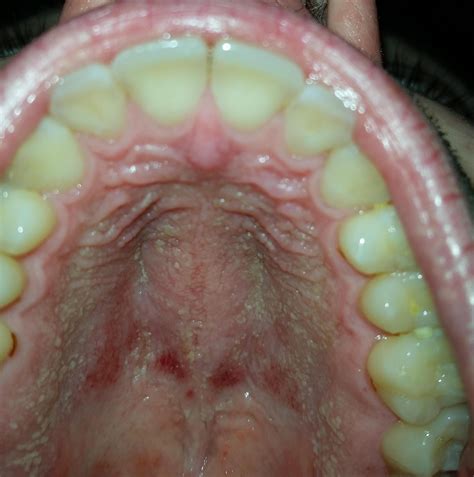

Experiencing a mouth palate itchy sensation can be quite uncomfortable and concerning. This symptom can arise from various causes, ranging from minor irritations to more serious health conditions. Understanding the potential reasons behind an itchy mouth palate is the first step toward finding relief and addressing any underlying issues.

An itchy mouth palate can be caused by a variety of factors. Some of the most common causes include:

• Allergic Reactions: Food allergies or sensitivities can trigger an itchy mouth palate. Common allergens include nuts, shellfish, and certain fruits.

• Oral Thrush: This is a yeast infection that can cause an itchy sensation in the mouth, including the palate.

• Dry Mouth: Insufficient saliva production can lead to an itchy or dry feeling in the mouth.

• Oral Lichen Planus: This is a chronic inflammatory condition that can affect the mucous membranes of the mouth, including the palate.

• Canker Sores: These are small, painful lesions that can develop on the palate and cause itching.

• Vitamin Deficiencies: Deficiencies in certain vitamins, such as B vitamins, can lead to oral discomfort and itching.

• Medication Side Effects: Some medications can cause dry mouth or other oral symptoms as side effects.